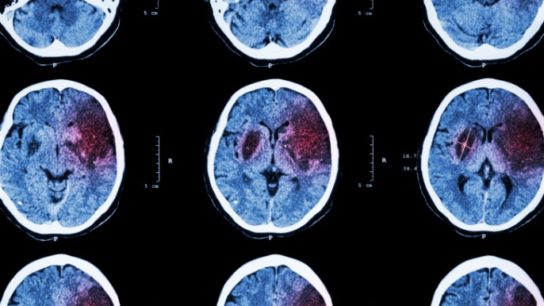

SPECT imaging can be more accurate in the diagnosis of traumatic brain injury and post-traumatic stress disorder than CT or MRI.